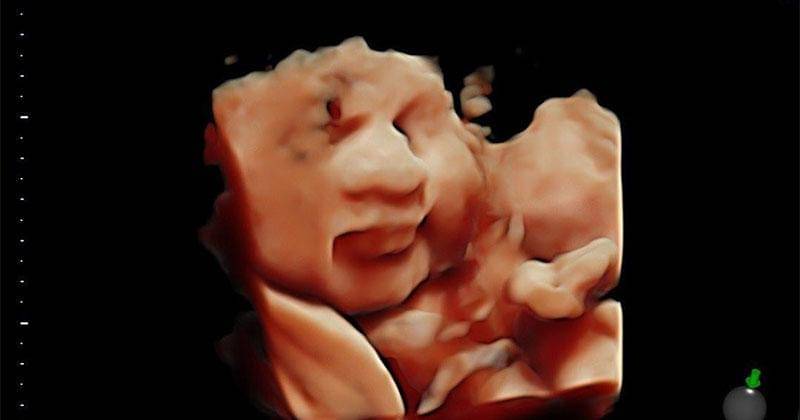

Anak Pertama Marcell Darwin Tersenyum dalam Kandungan. Kok Bisa?

Marcell Darwin dan Fasty Nabila termasuk salah satu pasangan artis yang sebentar lagi akan resmi berperan sebagai orangtua di pertengahan tahun 2020 ini. Kini usia kandungan sang Istri berada di fase trimester ketiga kehamilan bahkan sudah menjelang persalinan, tepatnya di minggu ke-36.

Demi memerhatikan kondisi kesehatan anak pertamanya, pasangan ini meluangkan waktu untuk memeriksakan kesehatan jelang persalinan ke dokter sekaligus melakukan ultrasonography (USG) untuk bertemu dengan si Kecil.

USG seringkali dilakukan oleh ibu hamil untuk melihat pertumbuhan serta memeriksa kondisi bayi sesuai dengan usia kehamilannya. Selain bermanfaat selama masa kehamilan, ada juga yang menarik karena kamera USG bisa saja menangkap beragam pose bayi selama berada di dalam kandungan.

Ketika melakukan USG di RSIA Bina Medika daerah Bintaro, anak pertama Marcell Darwin tampak tersenyum.

"Jagoan gue lagi senyum nih!" tulis Marcell Darwin di dalam sebuah foto unggahannya.

Anak pertama mereka seolah memperlihatkan raut wajah sedang tersenyum saat menjalani USG.